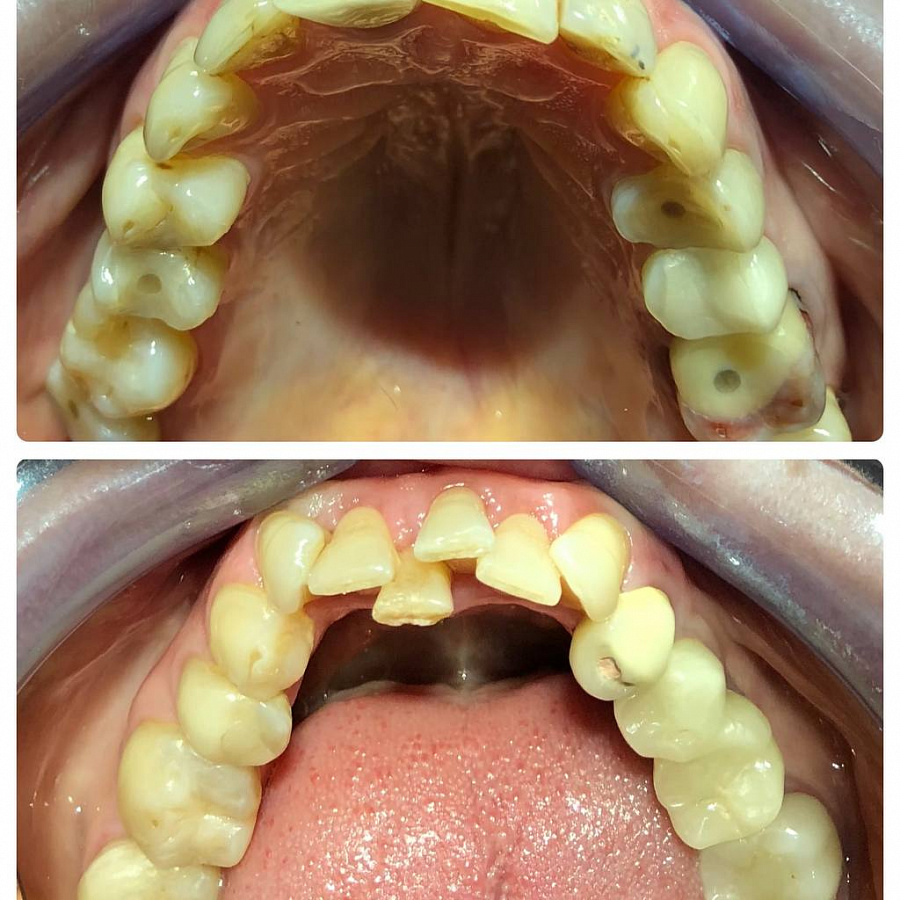

Пациентка обратилась с жалобами на эстетику всех зубов. Ранее уже были установлены постоянные коронки, имплант 34.

После диагностики пациентке было предложено провести комплексное лечение:

Санацию полости рта.

Ортодонтическое лечение.

Ортопедическое восстановление окклюзионных контактов и эстетики зубов.

Санацию проводил доктор Платонов. Далее провели удаления резца и ортодонтическое лечение с помощью брекетов, чтобы додготовить зубы к протезированию.

После доктор Мискевич провела протезирование, чтобы нормализовать прикус, изменить цвет и форму зубов.